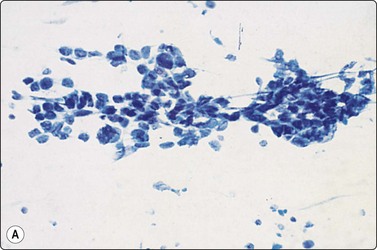

image

Fig. 8.25 Small cell carcinoma

Loose clusters with some dispersal and smearing artifact (Pap, HP).

Fig. 8.26 Small cell carcinoma

Pleomorphic poorly cohesive cells with little or no cytoplasm; nuclear molding (MGG, HP).

Fig. 8.27 Small cell carcinoma

Small loose cluster showing absence of cytoplasm, finely granular chromatin, inconspicuous nucleoli, nuclear molding and teardrop cells (H&E, HP).

Cell pleomorphism is so distinctive that a diagnosis of malignancy is seldom in doubt (Figs 8.25-8.27). The most immediate impression is the absence or sparseness of cytoplasm rather than the small size of the neoplastic cell (Figs. 8.26 and 8.27). In fact, the cell nuclei may appear larger than similar cells in sputum and this may mislead one into making a diagnosis of non-small cell carcinoma. This difference in size between sputum and aspirated material is due to degenerative changes and shrinkage in sputum. It is sparseness of cytoplasm rather than size which is the most helpful initial clue in differentiating the lesion from other pulmonary carcinomas.

The combination of dispersal with clustering is also important, especially when other small cell neoplasms enter the differential diagnosis (Fig. 8.25). Lymphomas generally do not display such cell cohesion, although large fragments may be dislodged, and in some cases lymphoid cells may form clusters or packets.

Fragility of nuclei is emphasized by tear-drop cells or streaks of smeared nuclear material,226 and the close nuclear apposition and molding so commonly seen in sputum are also evident (Figs 8.26 and 8.27). Uniform coarsely granular ‘salt and pepper’ nuclear chromatin is also a well-recognized feature of this cancer in other sites, but one point of difference from sputum is the frequency of small nucleoli in aspirated material; they are less commonly seen in sputum. This may also be related to the better preservation of cells removed directly from tumor; small nucleoli are also often seen in bronchial brush material. Mitotic figures are usually easily found.